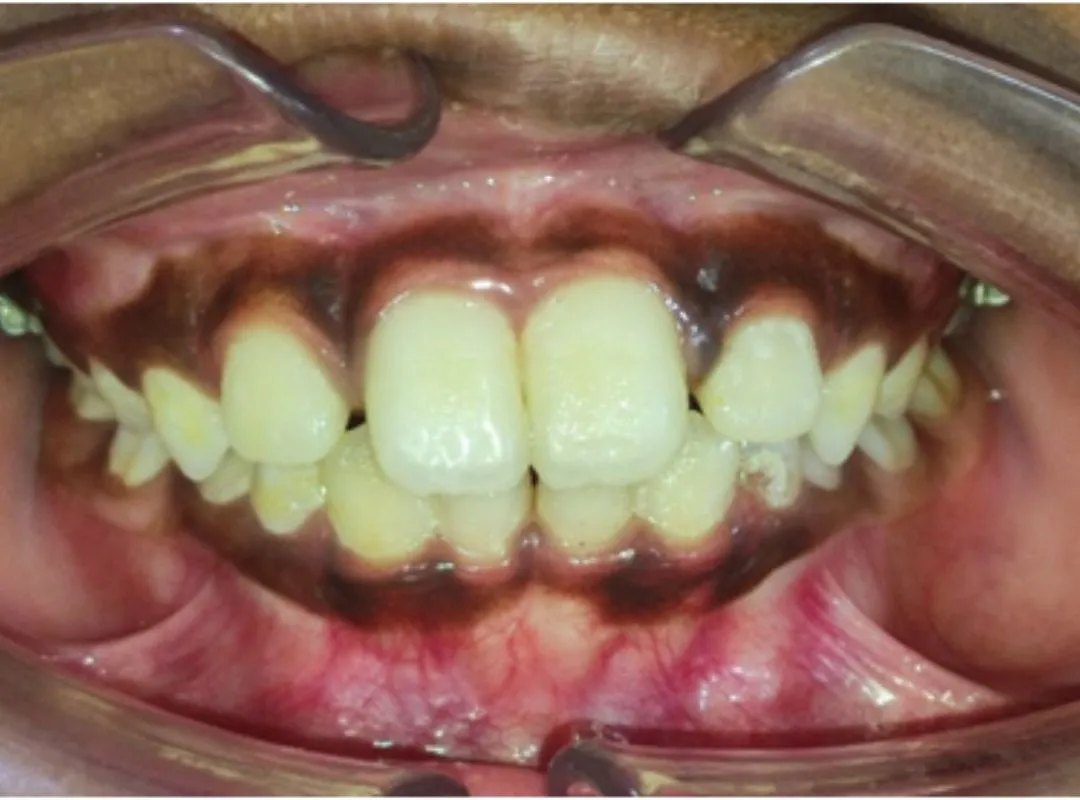

I had undergone my teeth Aligner process at JP dental, Perambur,which was over a period of 8 months. Journey was of 12 levels of aligners and after each level my teeth were thoroughly evaluated to ensure the process was smooth and progressive. The doctors here are very professional and have upto date equipments which gave me a very great outcome from my journey here. Highly recommend .create a caption for this review